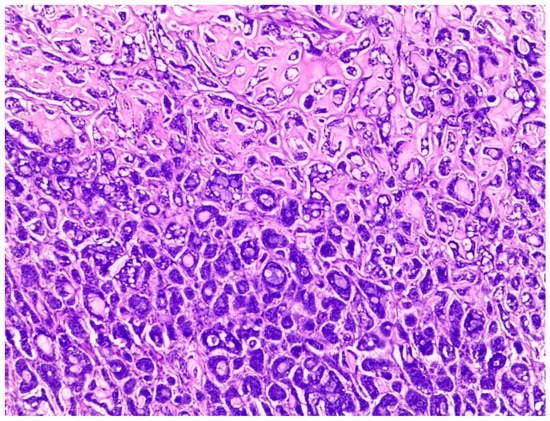

Histologically, salivary nonsolid AdCCs showed biphasic cell populations arranged in alternate cribriform and tubular architectures (Figure 1). The cribriform pattern demonstrated nests of neoplastic cells with hyperchromatic, angulated nuclei arranged in microcystic and macrocystic spaces. These pseudocystic cavities were occasionally filled with hyaline or basophilic mucoid material. The histologic features in the major salivary glands did not differ much from those in the minor salivary glands. However, solid nests of AdCC favored submucosal infiltration in the minor salivary glands (Figure 2, Case #15). Sinonasal AdCC revealed nests of cribriform and solid areas, while extensive hyalinization was recapitulating a jigsaw puzzle-like pattern (Figure 3). The cells of sinonasal AdCC were sometimes basaloid, with dark, hyperchromatic nuclei. The cells were typically arranged in a palisading pattern around the cystic spaces. A few salivary AdCCs revealed basaloid cells arranged in solid growth patterns that were insufficient for diagnosis as high-grade AdCCs. Mammary SB-AdCC revealed areas of cribriform, a solid growth pattern (>90%), and a basaloid appearance, with myxoid or hyalinized stroma. Ductules were present within the tumor islands. Small cysts and pseudoglandular structures were occasionally seen (Figure 4). This variant is characterized by the presence of small, basal-like cells with scant cytoplasm. The basaloid variant was associated with a higher risk of metastasis and a poorer prognosis. All neoplastic cells were positive for IHC SOX10, CK7, CD117, p63, and KI67. The clinical and molecular findings are shown in Table 1. There, all of the AdCC cases had MYB rearrangements detected by fluorescence in situ hybridization (FISH), which is a common genetic alteration observed in AdCC. Specifically, MYB was found to be fused with NFIB and/or KMT2C/KMT2D in AdCC cases from sinonasal and minor SG sites. MYB::NFIB fusion is a well-known molecular alteration that occurs in approximately 30–70% of AdCC cases and has been associated with better prognosis compared to cases without this fusion. On the other hand, MYB::KMT2C/D fusions were less common but have also been reported in cases from salivary and sinonasal AdCCs. Although this is the first study to report this finding, its clinical significance is yet to be fully elucidated. In addition to FISH, some AdCC cases were also analyzed using next-generation sequencing. In Table 1, NGS was performed in several AdCC cases from sinonasal, minor SG, and parotid gland sites. MYB::NFIB and MYB::KMT2D fusions were detected in these cases, which is consistent with the FISH results. Notably, some cases were not analyzable by NGS, which may be due to various reasons such as low DNA quality or quantity. The median score for Group 1 was 70 (IQR: 60–80), the median score for Group 2 was 85 (IQR: 75–90), and the median score for Group 3 was 60 (IQR: 55–70). The results indicate that there was a significant difference between Group 1 and Group 3 (p < 0.05) and between Group 2 and Group 3 (p < 0.05) but not between Group 1 and Group 2 (p > 0.05). This suggests that the solid mammary AdCCs with basaloid features (Group 3) have different characteristics compared to the other two groups.

Figure 1.

Salivary AdCC showed biphasic cell populations arranged in alternate cribriform and tubular architectures. Pseudocystic cavities were occasionally filled with hyaline or basophilic mucoid material (H&E stain; magnification ×5).